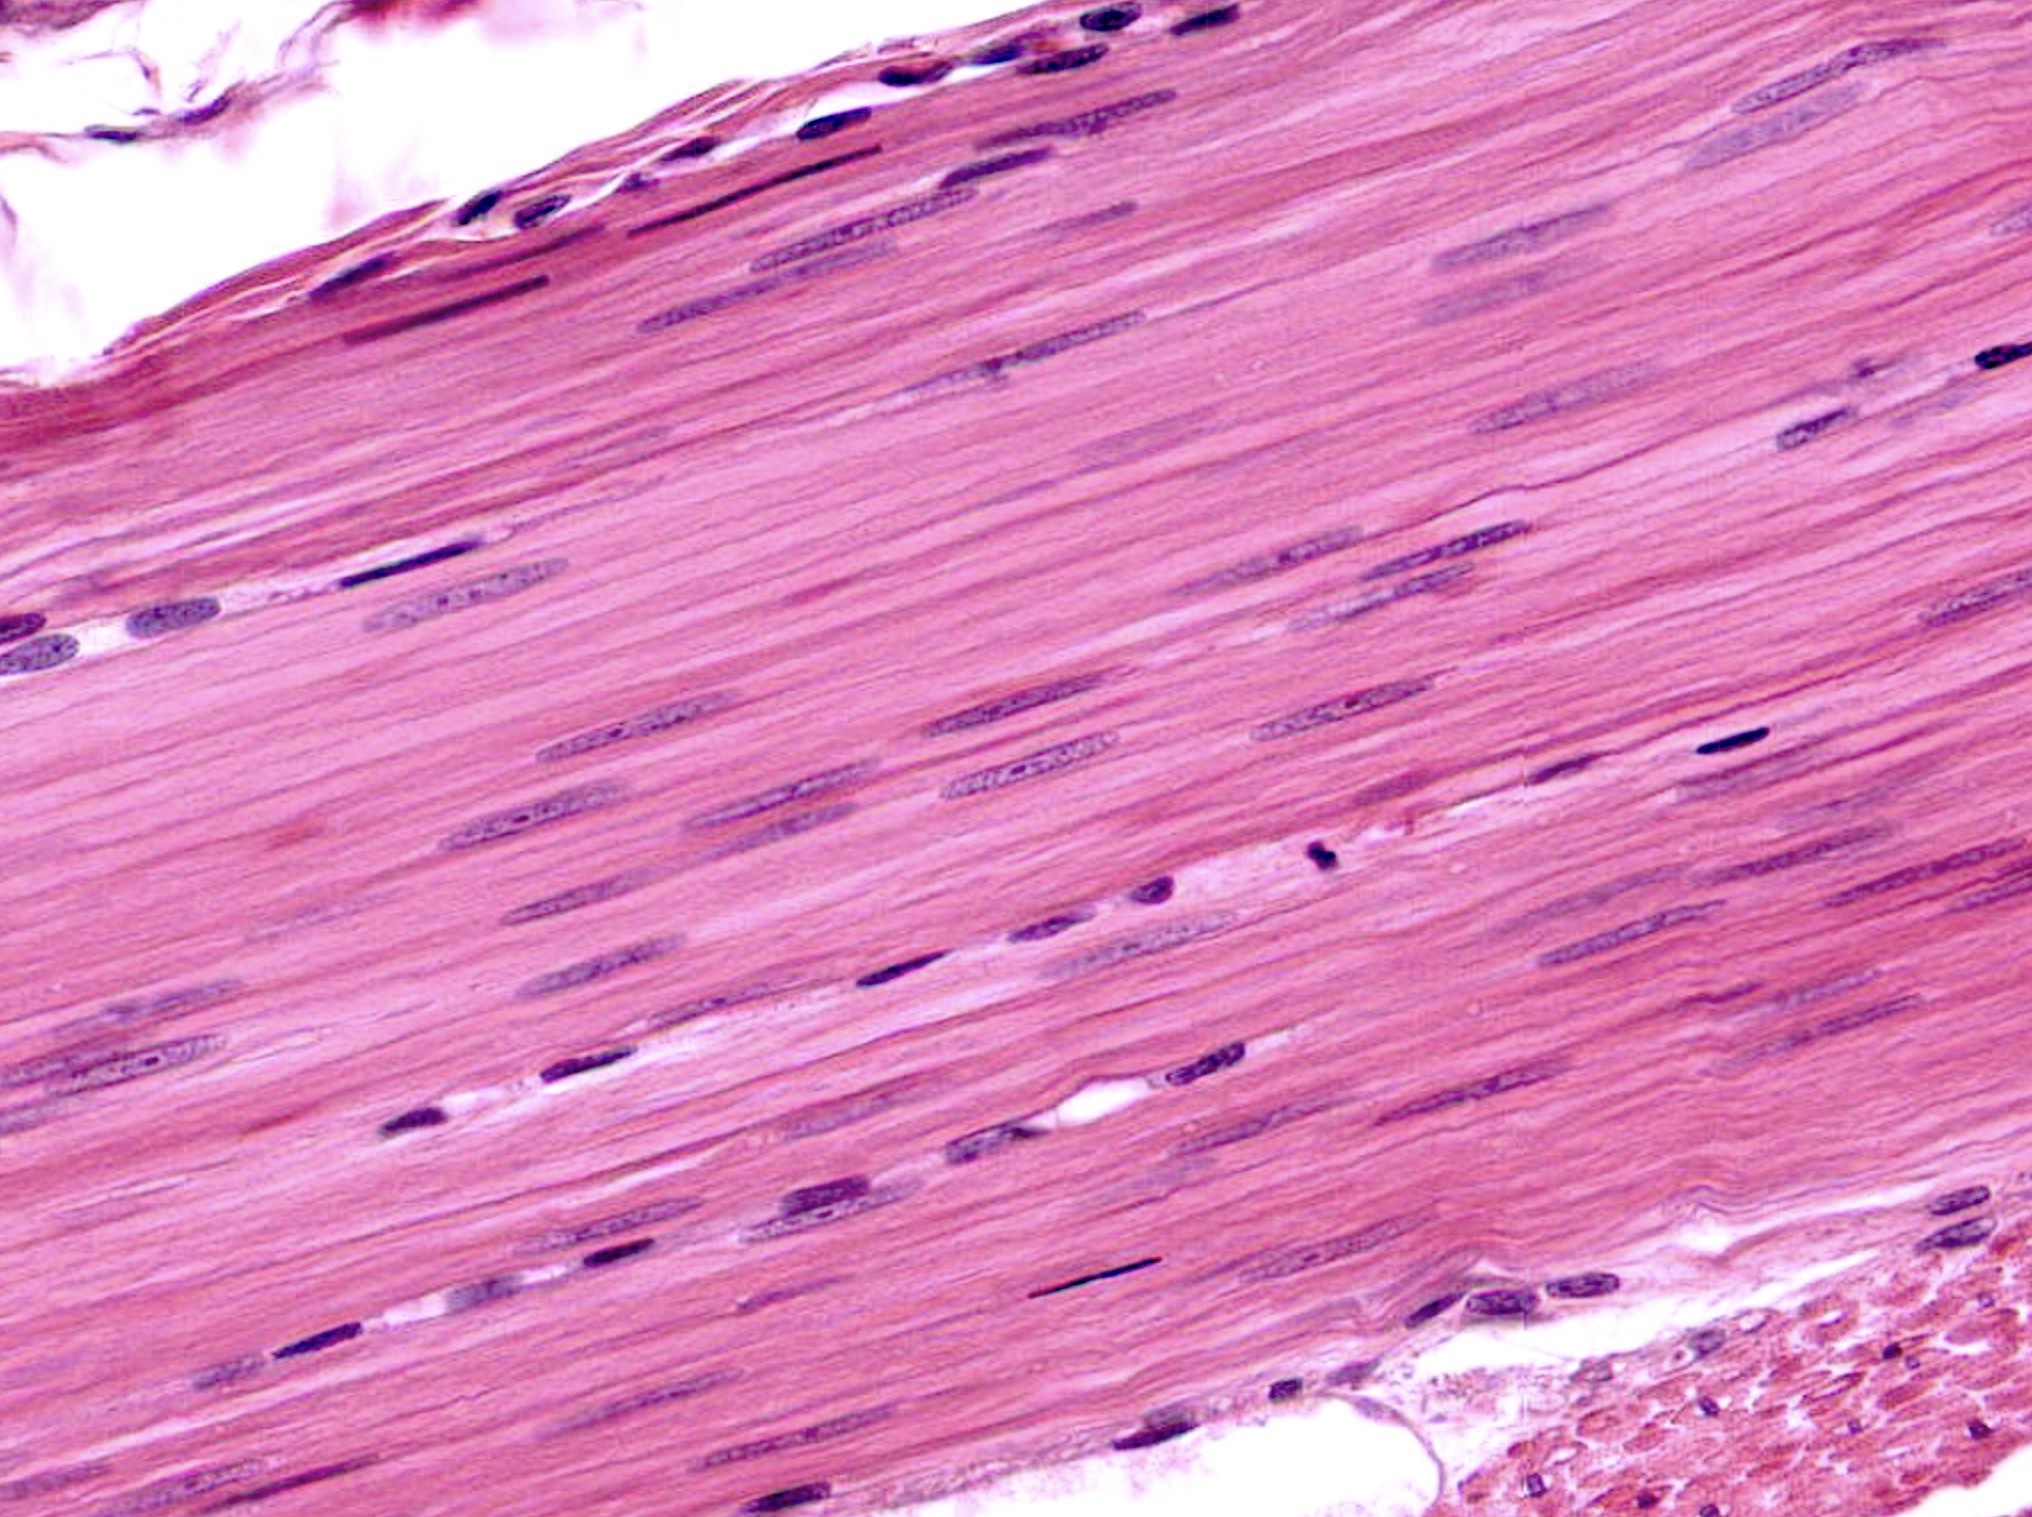

Skeletal muscle; rectus femoris